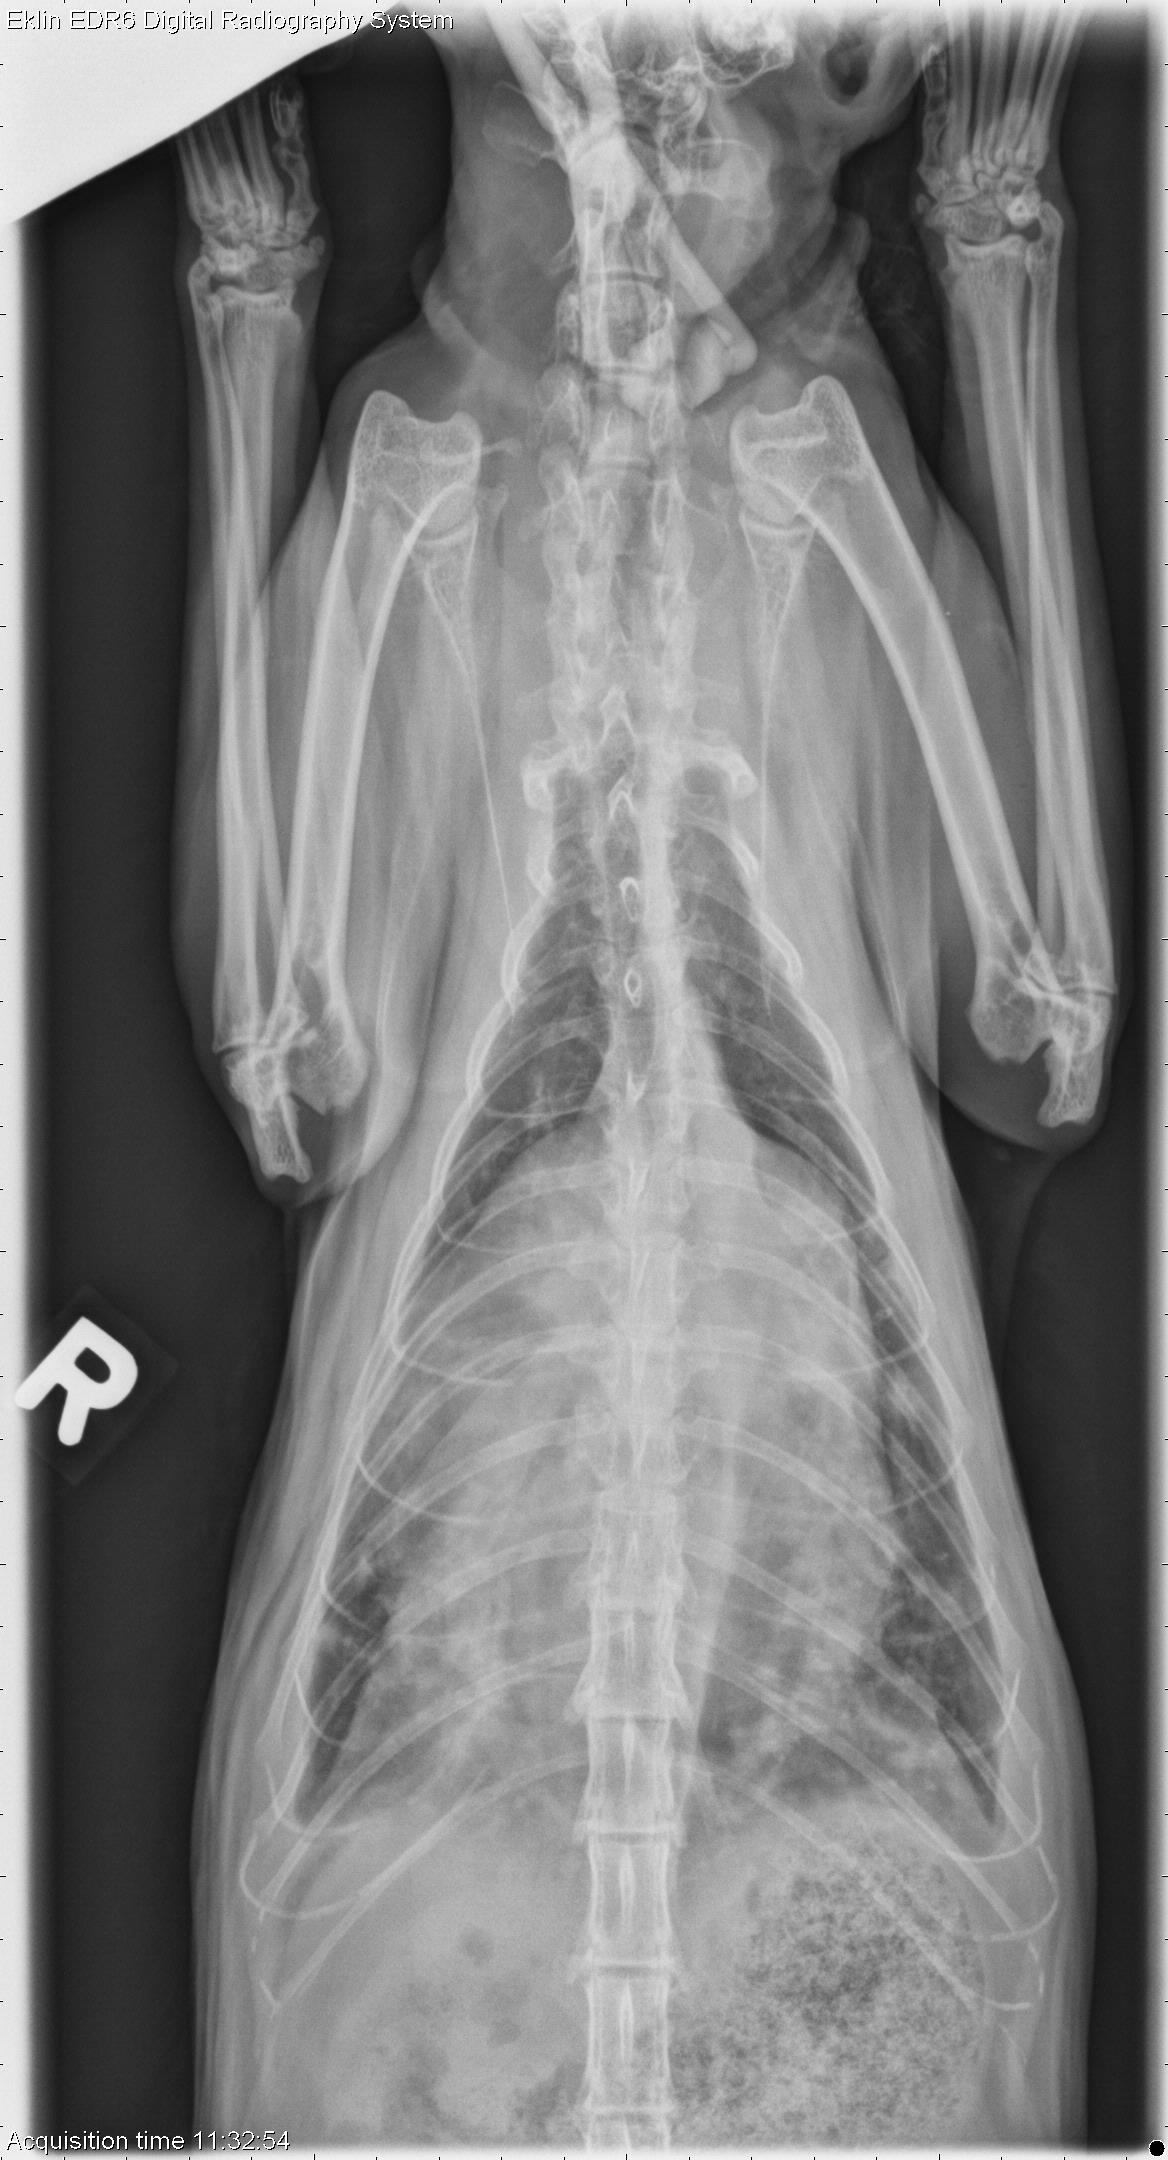

Peritoneal Pericardial Diaphragmatic Hernia Cat

Ppdh Peritoneal Pericardial Vetvital Veteriner Klinigi

Cat Breathing Problems Peritoneal Pericardial Diaphragmatic